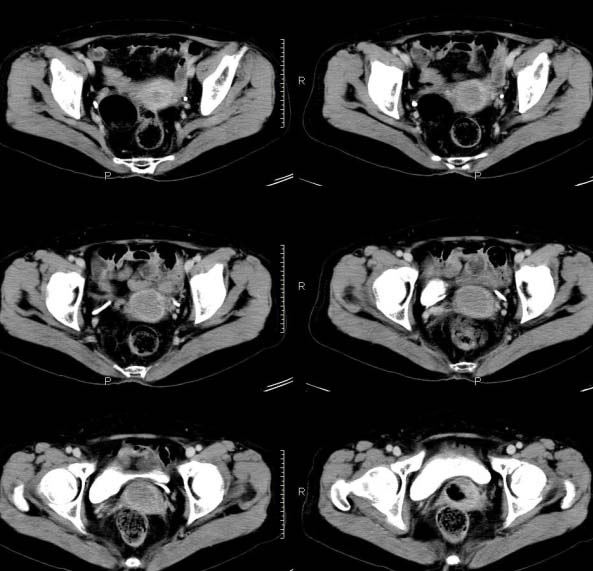

女,63岁,绝经15年,从阴道内有液体流出约1月余,且带有血,患者一般情况很差,在家属搀扶下行走。请大家看看是子宫病变还是宫颈病变?

子宫颈体积增大,宫颈壁不均匀性增厚,且不均匀性强化。考虑为宫颈ca。

子宫颈内见低密度影,外形不规则,不均匀强化,考虑占位,子宫颈癌可能性大。